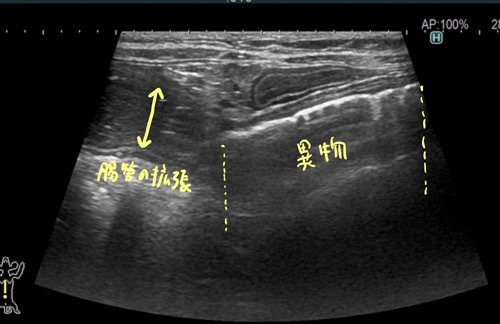

猫の小腸内異物(ジョイントマット)1 症例報告(高橋雅弘) 高橋ペットクリニック外科ケースより 猫の急性嘔吐と食欲不振 超音波検査において 小腸内に表面高エコーで音響陰影を伴っているため異物を疑います。 通過障害を疑う腸管の拡張が見られました。 以上の所見より小腸内異物と診断し、静脈内点滴を実施して緊急手術を行いました。 つづく!! « 前の記事へ カテゴリ一覧ページに戻る 次の記事へ »